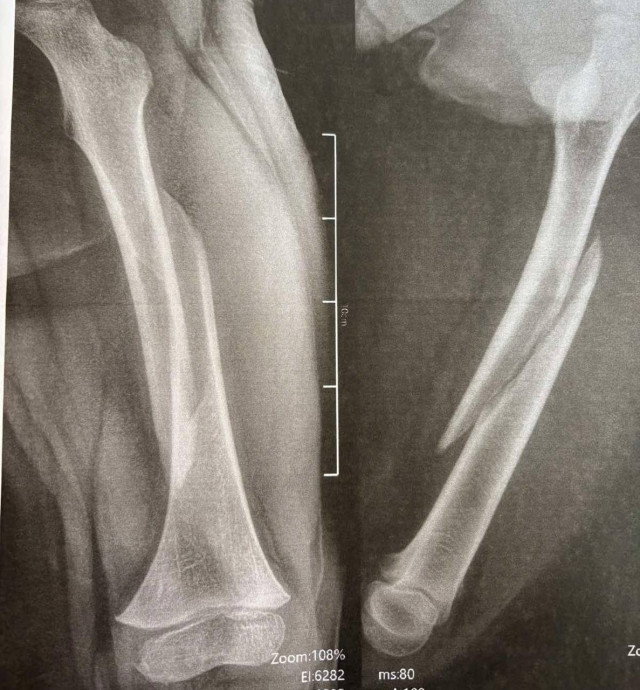

Наслідки падіння для 13-річного Максима – перелом стегнової кістки зі зміщенням і кісток гомілки.«Переломи дуже серйозні, – каже дитячий ортопед-травматолог Богдан Петерчук. – Попри це, завдяки інтрамедулярному остеосинтезу через два дні після операції Максим вже рухає ногою та швидко реабілітується. Оперативне втручання ми зробили через невеликі розрізи на стегні та гомілці».